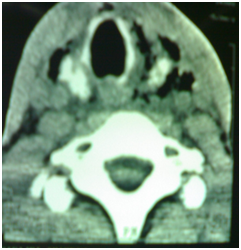

All six patients were symptomatic Four of patients were male. Age of patients was 65 to 80years. Four of patients came with dysphasia aspiration, halitosis, and malnutrition and regurgitation, one of this patient present three period with aspiration pneumonia and hospital admission. One of patients underwent endoscopic diverticulotomy and 24 hour after this procedure present with odynophagia, fever and neck subcutaneous emphysema With B-swallow perforation of diverticula was demonstrated, this patient underwent neck exploration and diverticulectomy and drainage. Diagnostic tools of five cases was B-swallow and esophagoscopy (Figures 1-5). One came with food marital retention and pain and neck mass tender mass. One patients referred with erithem, redness and criptation of neck with diagnosis of diverticulitis (Figures 6 & 7). Two cases underwent flexible endoscopic diverticulotomy, one failed and another ones complicated with perforation. The most common surgical approaches was diverticulectomy and myotomy in four patients (Figures 8 & 9). Food debris was present in one patient (Figure 10). Two of patients underwent diverticulectomy without myotomy. Complication and mortalities were zero. In two years flow-up, Outcome was good.

Figure 7 CT-scan of neck with subcutaneous Emphsema.

Zenker’s diverticulum (ZD) is an acquired sac-like out pouching of the mucosa and submucosa layers originating from the pharyngo esophageal junction and it occurs typical in the cervical esophagus. Zenker's diverticula (ZD) typically present in elderly individuals, especially during the seventh and eighth decades of life.4 But in our cases age of patients was less than other researches. Classical symptoms of Zenker's diverticulum (ZD) are progressive oropharyngeal dysphagia, regurgitation of food debris due to food retention in the diverticulum (one of our patient present with food entrapment in the diverticula), weight loss, stasis of secretion in pharynx, chronic cough, chronic aspiration, halitosis, sensation of a lump in the throat, (in our study one case present aspiration pneumonia and one with neck lump). Hoarseness, whistling and cervical borborygmi are seen in some patients.1,2 Complications of untreated ZD are diverticulitis, peptic ulceration, bleeding, iatrogenic perforations during passage of endoscopes or naso gastric tubes, fistulas, diverticulitis and vocal cord paralysis.2,3 One of our case admitted with esophageal perforation due to endoscopes stapler procedure and one admitted with diverticulitis. Cancer, probably has rarely been reported in association with Zenker diverticula (ZD), with an incidence of 0.5%.6 A barium swallow study is the first and the mainstay tools in diagnosis of Zenker's diverticulum, which show the size and location of (ZD), but a carefully esophagoscopy is mandatory to rule out malignancy.6,7 In our study all patients with dysphagia underwent A barium swallow and esophagoscopy to rule out malignancy, but one of our cases underwent CT-scan of neck for a mass.. Small asymptomatic diverticula do not need treatment, because the risk of severe complications, cancer and aspiration is low.7 Treatment needed for all symptomatic (ZD). Surgical procedures for ZD are open diverticulectomy with or without cricopharyngeal myotomy or diverticulopexy or diverticular inversion and myotomy alone.8 New procedures are endoscopic staple- assisted oesophago diverticulostomy,9,10 endoscopic CO2-laser myotomy.11,12 Endoscopic harmonic scalpel diverticulotomy.13,14 and flexible endoscopic diverticulotomy.15,16 It is a widespread belief that myotomy should always be part of surgical procedures.7. In our study we used diverticulectomy with cricopharyngeal myotomy in four cases without any complication and recurrence, diverticulectomy without cricopharyngeal myotomy in two patients. Diverticulectomy, diverticulopexy or inversion alone without myotomy are have the high rate of long-term recurrence in the absence of cricopharyngeal myotomy.17,18 But we did this procedures. In recentyears Less invasive approaches with new techniques and devices have been implemented.9,19,20 Flexible endoscopy and trans oral endoscopic treatment have been popularity over open surgery with a lower in mortality and morbidity.9,19,20 In medium sized diverticula (3-5cm). Endoscopic stapling diverticulotom is better than others less invasive approaches.21 In diverticula which longer than 6 cm represent a relative contraindication to endoscopic treatment because residual pouch may be too large to allow easy clearance of pouch during swallowing.15,22 Open surgical excision in very large diverticula may still be benefit, especially in younger, good surgical candidates as our cases.17,18 In cases of treatment failure or symptomatic recurrence, flexible or rigid endoscopy, can easily and successful.9,19,20 Open surgical diverticulectomy with myotomy provides radicality, eliminating any theoretical risk of carcinoma.14,23 Open surgical excision have a low morbidity mortality and recurrences and outcome is good as our cases we have not this complications.5,6,8,21